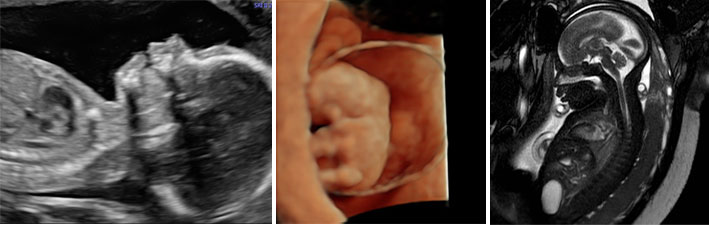

deib-rad.jpg

The radiology department at OHSU is committed to state-of-the-art imaging for pregnant patients in order for them to have choices for their reproductive health.  We work closely with the Section of Family Planning as well as all providers taking care of all pregnant patients. We are the imaging experts embedded in the Fetal Care and the Fetal Surgery Program. Our goal is to provide timely advanced imaging for our patients throughout pregnancy.